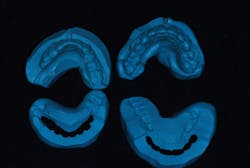

We take a full series of photographs and use a facebow to mount high-quality study models on a semiadjustable articulator in centric relation. Once we have this data, we can begin the treatment-planning process.

As we develop a treatment plan, we do the case four times: (1) in our minds, (2) in wax, (3) in provisionals, and (4) in porcelain.

We will also have started to develop a plan for the best approach to achieve each objective. Once the plan is finalized, we’re ready to move on to wax and translate that mental image into a 3-D reality using wax and stone. There is a specific sequence to this process:

- Establish the lower incisal edge position in harmony with the plane of occlusion.

- Build the upper incisal edges to the position derived from the 2-D analysis.

- Place the models on the articulator and complete the wax-up to provide equal intensity stops on all teeth, with anterior guidance that prevents posterior interferences in all directions of mandibular movement.

Throughout this process, we can determine if we need to increase the vertical dimension of occlusion, and discover the best way to balance the occlusion either by selective reduction or restoration of teeth. Our goal is always to do the least amount of dentistry necessary to get the best results.